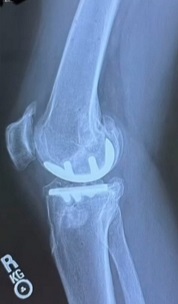

Parlo per esperienza diretta e dopo aver visto che le sue lastre sono identiche alle mie. La testa della tibia è stata piallata per poter inserire un piatto di sostegno ad uno spessore di plastica che fa le veci della cartilagine. Sulla testa del femore è stato inserito un cavallotto tondo a copertura. Questi due inserti sono fissati nelle ossa mediante perni. Ecco, questi perni, in caso di incidente serio, possono frantumare le teste del femore e tibia.

Da un articolo d Humanitas

Gli sportivi che praticano discipline invernali in modo agonistico possono sperare di tornare a gareggiare ad alto livello? «Sì, come ho accennato prima, con la dovuta riabilitazione e preparazione le abilità possono essere recuperate. Nel caso di protesi all’anca si può tornare al 100%, mentre un po’ più bassa è la percentuale che riguarda il ginocchio. Bisogna però sempre ricordare che essendoci un corpo estraneo – la protesi – le probabilità di infortunio sono molto più alte. Soprattutto, c’è il rischio di incorrere in fratture peri-protesiche: l’osso che si trova attorno alla protesi corre un rischio maggiore di fratturarsi rispetto alla stessa porzione di osso della persona senza protesi».

Le immagini qui sotto le aveva pubblicate la Vonn sulla sua pagina FB (cambia la gamba ma sono identiche alle mie)

Immagine:

15,11 KB

9,06 KB |